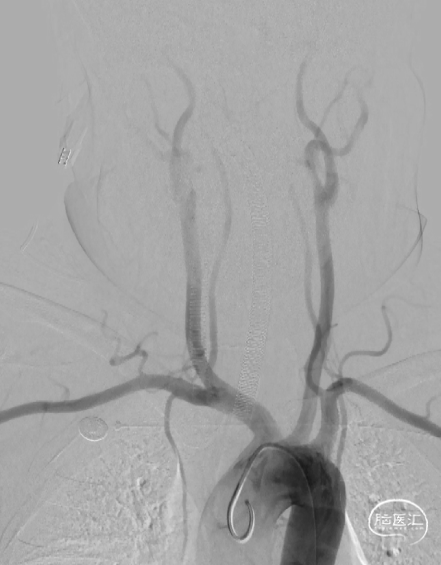

DSA

弓部造影显示双侧颈动脉、椎动脉血流通畅,右侧颈内动脉交通段可见动脉瘤。

右侧颈内动脉造影,可见后交通动脉瘤,大小约为4mm*6mm动脉瘤,瘤颈宽3.6mm。后交通血流通畅,大脑前动脉及大脑中动脉血流通畅。